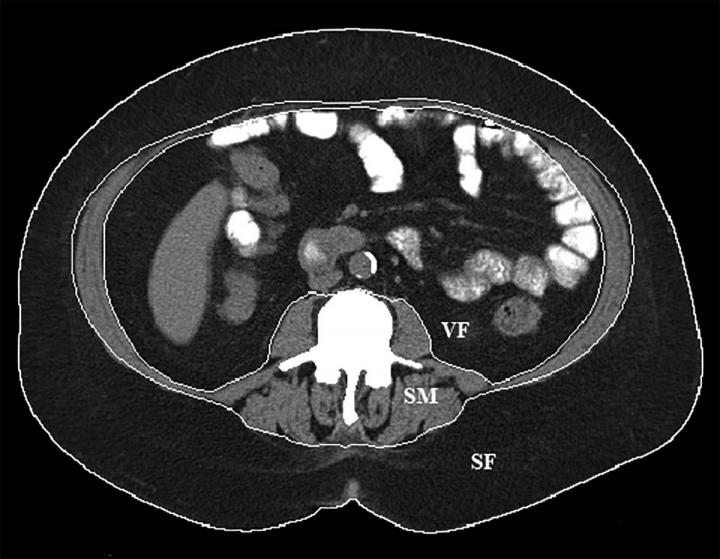

image: Body composition segmentation at the L3 lumbar vertebral body level. Boundaries for subcutaneous fat (SF), visceral fat (VF) and skeletal muscle (SM) are delineated by the white lines.

To learn more, Dr. Takahashi and colleagues studied CT scans of 16 overweight or obese patients who had undergone left gastric artery embolization to treat gastrointestinal bleeding. CT scans, when used in conjunction with special software, allow for measurements of body composition based on the different densities of tissues like fat and muscle.

While the weight loss was not surprising to the researchers, the changes in body composition were. The skeletal muscle index, a measure of the amount of muscle that connects to the skeleton and helps move the limbs, fell by 6.8 percent. Skeletal muscle is important to health, and loss of it can impair physical function and metabolism and put a person at higher risk of injury.

The patients also lost a significant amount of body fat. Their overall body fat index dropped by an average of 3.7 percent. However, much of the fat loss was subcutaneous, or the fat that lies directly under the skin. Visceral fat, the more dangerous fat surrounding the organs and associated with serious health problems like heart disease and diabetes, did not decrease significantly over the course of follow-up.